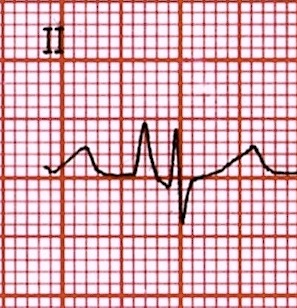

E por que é importante frisar-se isto? Porque um paciente pode ter onda P, mas ela ser resultado de uma estimulação atrial que não seja oriunda do nó sinusal. Exemplo:

Neste caso acima, nitidamente o estímulo não vem do nó sinusal.